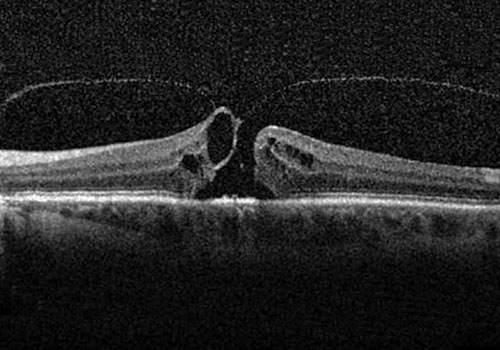

Il foro maculare è una patologia caratterizzata dalla formazione di una soluzione di continuo nella parte centrale della macula ed è associato ad una riduzione della capacità visiva.

Le adesioni vitreomaculari, i fori maculari lamellari e gli pseudofori possono rimanere asintomatici e non progredire. In questi casi è comunque consigliato eseguire periodicamente controlli del fondo oculare e un esame OCT. Una percentuale di casi tende invece ad essere sintomatica e a progredire nel tempo per cui si deve prendere in considerazione la possibilità di ricorrere ad un trattamento chirurgico.